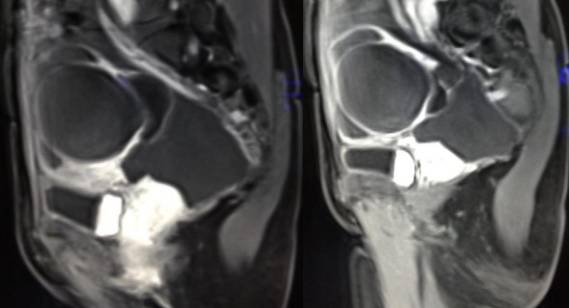

女性,42岁。

主诉:下腹部胀痛不适1月余

病史:自诉13岁时患“结核”,8年前行“左侧附件包块”切除术。

MR检查:

病理结果:黄体血肿

黄体血肿为正常排卵过程中,卵泡层破裂,引起出血,较多的血液潴留在卵泡或黄体腔内形成血肿。

正常黄体直径为15mm左右,以后转变为白体,并在下一个周期的卵泡期自然消退。若黄体内出血量较多,则形成黄体血肿,或称黄体内出血,出血性黄体。黄体血肿多为单侧,一般直径为40mm,偶可达100mm,黄体血肿被吸收后可导致黄体囊肿,较大的血肿破裂时可出现腹腔内出血,剧烈腹痛、少量阴道流血和腹膜刺激征,不易与宫外孕区别。

根据时间不同MR信号也有所不同,TIWI脂肪抑制序列可以鉴别脂肪和出血。